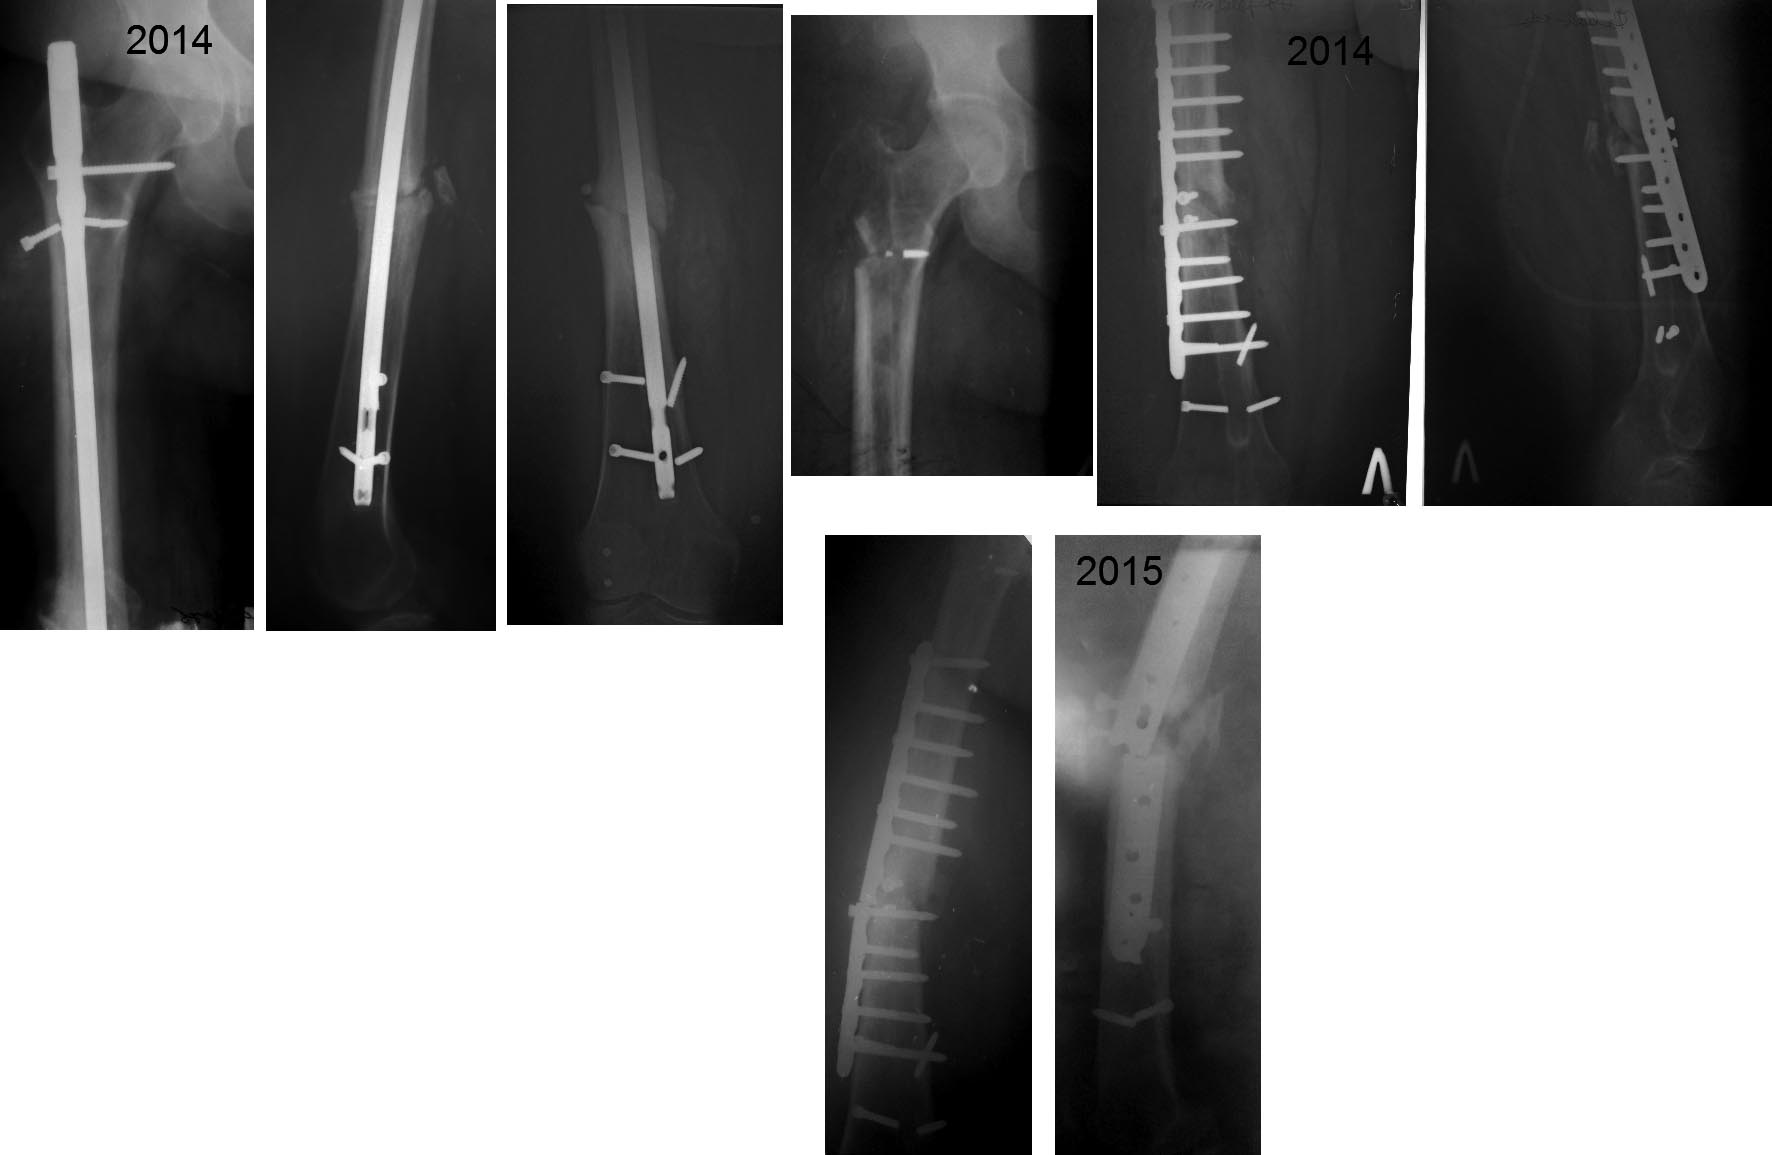

Несращение бедра-выбор метода

Пациентка К.40 лет ,вес- 130кг, рост 170 см, курит, С.Д. 2

тип-компенсированный. Травма в рез. ДТП 2008 г.- БИОС.

Август 2014 г.-удаление стержня (судя по снимку с немалыми

трудностями),костная аутопластика, МОС пластиной заживление первичное.

Поступила 29 09 2015 с несращением перелома и переломом фиксатора.

СОЭ-16, Лейк-11.0.

Предварительный план обследования и лечения:

1.Исключить(подтвердить) наличие инфекции. Какой алгоритм,

в сомнительных случаях, используете Вы?

2.Фиксация перелома длинной Gamma или PFNа с (или

без) антибактериальной мантией (склоняемся к данному методу, однако

настораживает потенциальный риск инфекции).

3.Аппаратный метод лечения (со своими достоинствами и

недостатками).